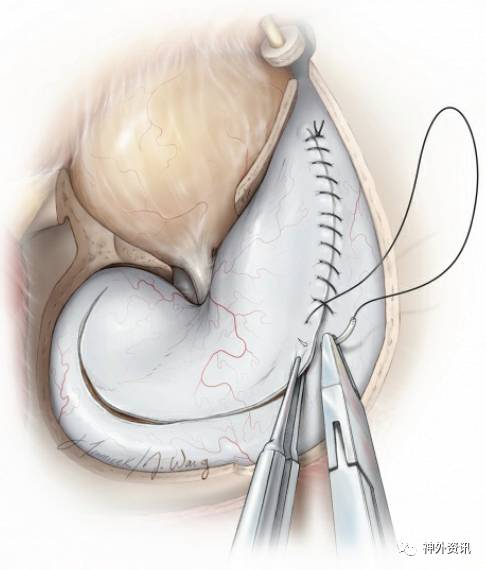

图39:半圆形切开硬膜,基底指向眶尖。该切口的目的在于暴露颞上回、侧裂和额下回。注意须将额部切口延伸至骨窗拐角处,以便充分利用额下空间。

图40:用数根缝线牵拉硬膜,以利于暴露。缝合点应靠近硬膜辦基底部,而非其边缘,这样可以最大程度地牵开眶内容物、颞肌等软组织,以充分利用硬膜内额下径路。